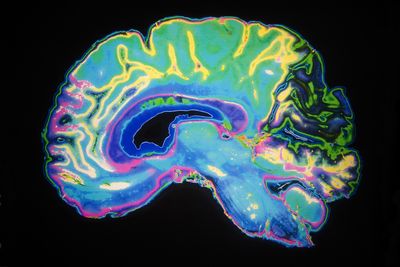

The rest of this article is behind a paywall. Please sign in or subscribe to access the full content.Lecanemab is a monoclonal antibody that works by actively removing sticky gunk, known as amyloid-beta, that builds up in the brains of people with Alzheimer's. During an 18-month trial of almost 1,800 people with early Alzheimer’s, they found that the drug slowed cognitive and functional decline by 27 percent.